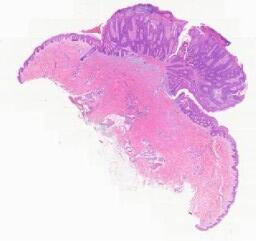

临床资料: 患者,男性,61岁,发现右侧睾丸肿大4+年。专科检查:右侧阴囊及睾丸肿大,局部皮肤无红肿,皮温正常,右侧睾丸约鹅蛋大小,质地硬,表面光滑,可活动,左侧正常,双侧腹股沟未扪及明显淋巴结肿大,透光实验阴性。术中见:睾丸鞘膜内少许淡黄色渗液约10ml,睾丸色呈灰白,质地硬,附睾稍增大。彩超检查:右侧睾丸大小约3.6×4.5cm,形态饱满,内回声不均质。其内扪及大小约3.2×3.7cm的混合回声团块,边界可见,形态较规则,内回声不均质,其内可见0.3×0.3cm的强光斑,后伴声影,团块内及周边可见丰富血流信号。提示:右侧睾丸混合回声团块?盆腔CT:右侧阴囊见约4.8×3.5cm不均质密度团块影,内见高密度结节影。考虑占位病变,检查提示睾丸肿物。

大体所见: 送检灰白灰褐色不规则组织一块,大小约8.7×6×3.5cm,切面可见灰白间灰黄色包块一个,大小约5×4.5×3.5cm,切面灰白灰黄色,质中等。